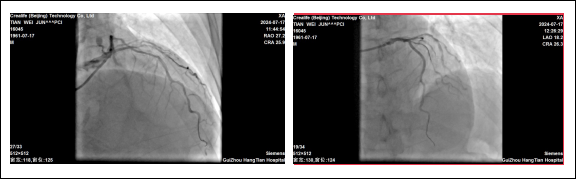

贵州航天医院心血管内科 应用国产冲击波球囊系统 完成严重钙化病变手术 近日,我院心血管内科团队成功为一名急性心肌梗死合并冠脉重度钙化患者实施了“冲击波球囊术”。手术取得了显著效果,术后患者症状明显改善。 63岁田先生,因胸痛2小时就诊我院心血管内科,经冠脉造影检查,提示:冠脉前降支的近中段弥漫性狭窄约80%-95%,局部明显“钙化影”。血管内的钙化病变就是导致患者胸痛的根本原因。 术前:前降支冠脉弥重度狭窄,伴钙化。 术中:冲击波球囊释放脉充、扩张。 心血管内科姜黔锋团队经过认真研究病情、冠脉造影图像,考虑到老年患者冠状动脉钙化重、血管迂曲的情况,进行常规冠脉旋磨风险大,单纯球囊扩张,难以取得满意的效果,在衡量多种手术方案,取得患者及家人同意后,决定采用血管内冲击波球囊治疗技术进行治疗,重点解决因冠脉重度环形钙化,直接支架植入贴壁不良,支架内在狭窄,急性血栓形成影响远期预后等的问题。 术后:支架植入后,血管畅通,效果良好。 针对此情况,由沈万贵主任担任术者,通过双导丝、预扩张球囊等进行预处理后,精准将冲击波球囊送至病变处,经释放脉冲后,OCT(经光学相干断层扫描的冠状动脉血管内影像)证实钙化病变已经完全打开,后扩张球囊充分扩张钙化病变处,很快达到了理想的手术条件,顺利完成支架植入。术后患者血管狭窄消失,血流通畅,胸闷、胸痛症状明显缓解,达到了预期的治疗效果。 我院心血管内科首次应用国产冠脉冲击波治疗系统完成手术,凭借丰富的手术经验和技巧,助力患者重获新生,标志着我院心血管内科冠脉血管钙化病变介入治疗技术再上新台阶,将为更多复杂、严重冠脉钙化患者带来“心”希望。未来,心血管内科团队将继续开拓进取,紧跟学科前沿,积极应对人口老龄化、心血管疾病复杂化,努力为患者提供规范、高质量的医疗诊疗技术服务。 延伸阅读 01 什么是冲击波球囊技术? 冲击波球囊技术,或称血管内碎石术,源自泌尿系统结石治疗的碎石原理,经过结合球囊成形技术的创新发展,成为一项新的治疗技术。 采用声压力波有针对性地作用于冠状动脉内膜及中膜下的钙化病灶,在不影响血管内膜完整性的情况下,有效地震松或震裂钙化病灶,恢复血管顺应性,为后续冠脉支架的植入提供更理想的管腔。 02 冲击波球囊技术的优势? 1.能够在不损伤血管壁的情况下,有效碎裂钙化物质,提高血管顺应性,为后续的支架植入手术创造更好的条件; 2.术中血管夹层、穿孔、远端栓塞、慢血流、无复流等并发症风险显著降低; 3.操作简便、安全性高、疗效显著; 4.是目前唯一能够有效处理浅层和深层钙化的技术。 贵州航天医院心血管内科简介 贵州航天医院心血管内科是遵义市市级重点专科,遵义市远程心电示范中心,遵义市高血压慢病管理示范中心。近年来成功获得胸痛中心标准版、房颤中心标准版,儿童先天性心脏病定点救治单位授牌,编制床位60张,科室配置了29台24小时动态心电图、110台24小时动态血压、心脏除颤仪、监护仪、输液泵、微量注射液,同步12导联、18导联心电图机、临时心脏起搏器、床旁血糖仪、主动脉内球囊反搏、食道超声、血管内超声诊断仪及DSA心血管诊疗等。 开展了急诊冠脉介入诊疗,冠脉复杂病变介入术、冠状动脉斑块旋磨术、心脏再同步治疗起搏器植入术、心脏再同步治疗除颤器植入术、射频消融术【心房颤动(导管消融、冷冻消融)、心房扑动、房性心动过速、室性心动过速、室性早搏】、结构性心脏病介入治疗【房间隔缺损(卵圆孔未闭)封堵术、室间隔缺损封堵术、动脉导管未闭封堵术、冠状动脉瘘封堵术、左心耳封堵术等】、临时起搏器植入术、常规永久起搏器植入术(双腔、单腔)、下肢动静脉造影术、下腔静脉滤器植入及取出术、自主肾上腺静脉采血、颈动脉支架植入术、外周动脉支架植入术、肾动脉支架植入术等,积极开展冠脉内超声检查、FFR、OCT、心脏射频三维手术,同时开展了房颤一站式治疗(房颤射频消融术+左心耳封堵术)、主动脉瓣介入术等,在外院专家指导下完成腹主动脉支架植入术。 心血管内科门诊时间及地点 心内科门诊地点及就诊时间 门诊一楼012/013诊室 周一至周五(08:00-17:00) 周六、周日及节假日(08:00-16:00) 心内科咨询电话 一、病房护士站:0851-28611793(外科综合楼9楼) 二、医生办公室:0851-27677832 三、心内科门诊:0851-28614631 四、心内科总值班电话:17785233019 科室专家 注:部分图片来源于网络,如有侵权,请联系删除。 精彩推荐 供 稿:曹昌强(心血管内科) 编 辑:唐语蔚 一 审:沈万贵(心血管内科) 二 审:陈 伟 三 审:蒙昌耀